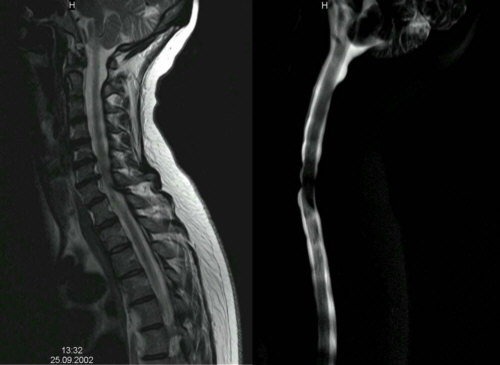

MRT der HWS bei cervikalem Bandscheibenprolaps